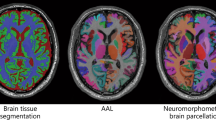

The DTI data were motion and eddy current corrected using the FLIRT and FUGUE algorithms from Free-Surfer Library (FSL) (http://www.fmrib.ox.ac.uk/fsl), and an additional geometric distortion correction was performed. The DTI images were then co-registered to the T1 image and up-sampled to the T1 resolution. Fractional anisotropy (FA) maps were calculated using the teem algorithms (teem.sourceforge.net). An unbiased project specific FA atlas in MNI152 space was generated from the all images using the fast, high degree diffeomorphic image registration algorithm (DARTEL) implemented in SPM8 (http://www.fil.ion.ucl.ac.uk/spm). The FA maps of all subjects were warped onto the FA atlas using DARTEL. Labels from the ICBM DTI81 atlas (created by hand segmentation of a standard-space average of diffusion MRI tensor maps from 81 healthy subjects) were used to extract mean FA values from the six white matter tracts of interest (Fig. 1), voxels with FA < 0.2 were masked out to reduce partial volume effects from neighboring gray matter regions. The mean FA values from the left and right tract were combined after excluding a hemispheric effect.

Veterans with PTSD were compared to combat-exposed controls on six, long associational white matter tracts using ANCOVA (Table 2 and Fig. 2), covarying for age and comorbidities (LOC < 10 min and cardiometabolic diagnoses). The PTSD group exhibited significantly higher FA values relative to controls in the SFOF tract (p = .034) and borderline higher FA in the ACR (p = .054) and CGC (p = .077), while controlling for age and comorbidities. No differences were present in the UF, IFOF or SLF. Age was not a significant predictor, potentially due to relative youth of the sample (mean age: 33 years; range: 22–55). Medical comorbidities, including LOC and cardiometabolic diagnoses, were a significant predictor of higher SFOF FA, independent of PTSD.